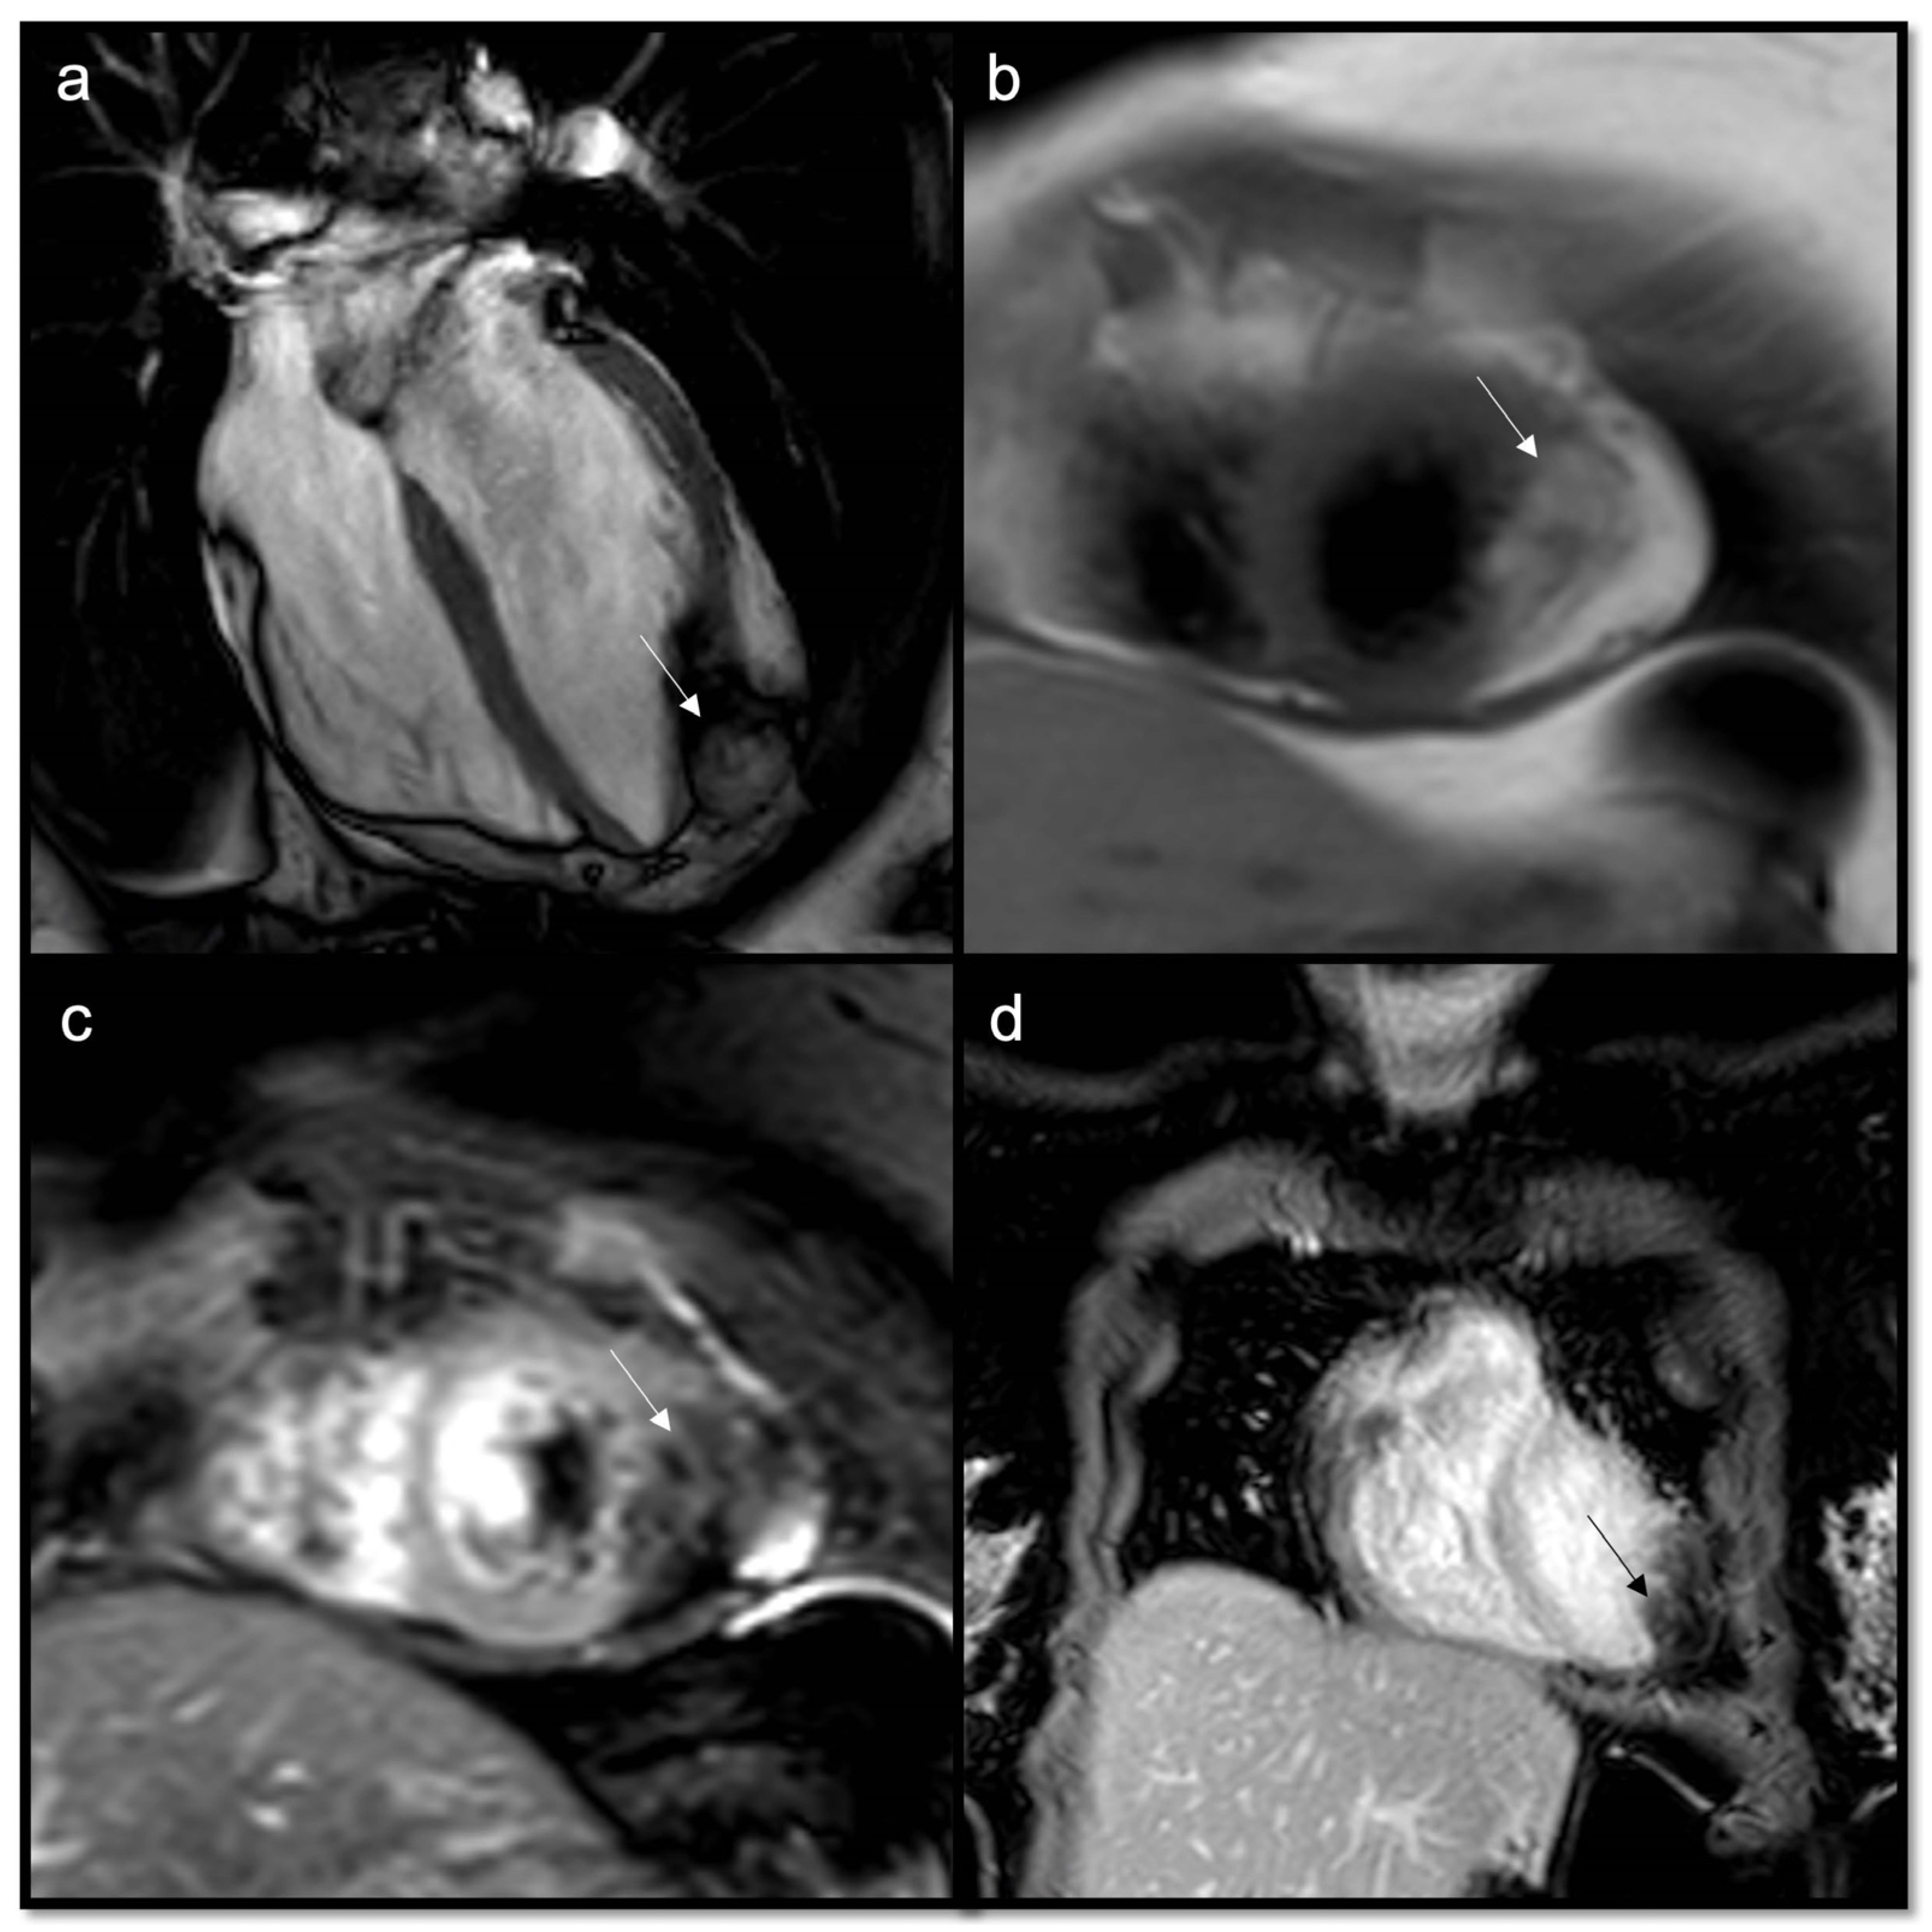

Figure 7.

Typical myxoma (arrow) appears as a well-defined, smooth, oval, or lobular lesion, has an intermediate signal in T1w (a), heterogeneous hyperintensity in T2w and T2w Fat Sat (b,c), linked to the high presence of water in the myxoid stroma. It shows limited enhancement on first-pass perfusion sequences (d) and progressive heterogeneous enhancement on late gadolinium enhancement (LGE) sequences due to its fibrous content (e,f). Some cases may show hyperintensity on T1w images due to hemorrhagic foci. Cine imaging is of particular value in this case as these lesions can be highly mobile and prolapse through the atrioventricular valves during diastole, causing temporary obstruction to blood flow.